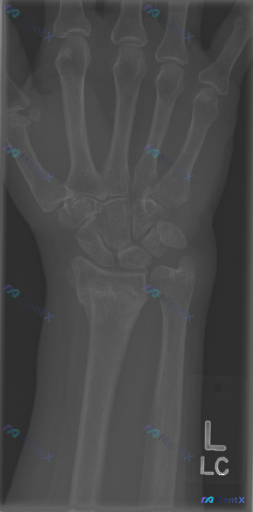

整理到一份左手腕正位(AP view)X光的影像分析资料,客观征象如下: 主要影像表现 - 骨性结构:各腕骨形态规则、序列整齐,无明显脱位或皮质中断;尺骨茎突完整;左侧桡骨远端背侧皮质连续性中断,可见透亮线,骨折线延伸至桡腕关节面。 - 骨密度:骨小梁清晰,无明显广泛性骨质疏松,未见溶骨性破坏、肿瘤...